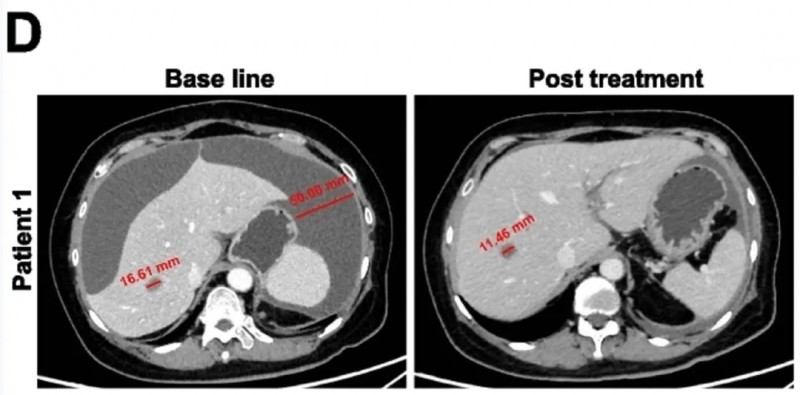

全球首创国研KT032 CAR-T暴击卵巢癌/间皮瘤,首次人体临床试验疾病控制率达100%

KT032是全球首创的国研新型靶向间皮素(MSLN)的CAR-T细胞疗法,属于多链DAP-CAR-T技术路线。在体外细胞杀伤试验与异种移植模型中,该疗法(尤其由自然杀伤细胞免疫球蛋白样受体截短体与DAP12结合形成的多链DAP-CAR-T),相比其他由DAP12、DAP10或CD3ζ相关自然杀伤细胞激活受体介导的CAR-T,展现出更优的细胞毒性与肿瘤杀伤能力。近期,KT032公布首次人体临床试验的振奋数据——在卵巢癌与间皮瘤患者中,疾病控制率(DCR)达100%。

该研究共纳入8例晚期难治性患者(7例卵巢癌、1例间皮瘤),所有患者均至少接受过2种标准治疗(如化疗、靶向药)后复发或进展,且经病理确认肿瘤细胞MSLN表达≥15%(MSLN为KT032的精准靶点)。

结果显示:8例患者疾病控制率达100%,无1例出现快速进展,意味着CAR-T细胞成功抑制肿瘤进展;其中2例实现“部分缓解”(肿瘤缩小≥30%),部分缓解率33.3%;4例达到“疾病稳定”(肿瘤未增大或略有缩小),6例肿瘤得到有效压制。生存数据同样亮眼,患者中位无进展生存期(PFS)达5.5个月,中位总生存期(OS)达10.5个月,远超同类患者预期生存时间。此外,部分患者治疗后癌抗原125(CA125)水平显著下降,整体治疗有效率远超传统方案。

值得关注的是,两位患者的疗效尤为突出:患者1肝转移灶缩小31%,且腹腔积液完全消失;患者2可测量病灶总最大直径缩小42%(详见下图)。

▲图源“BMC”,版权归原作者所有,如无意中侵犯了知识产权,请联系我们删除